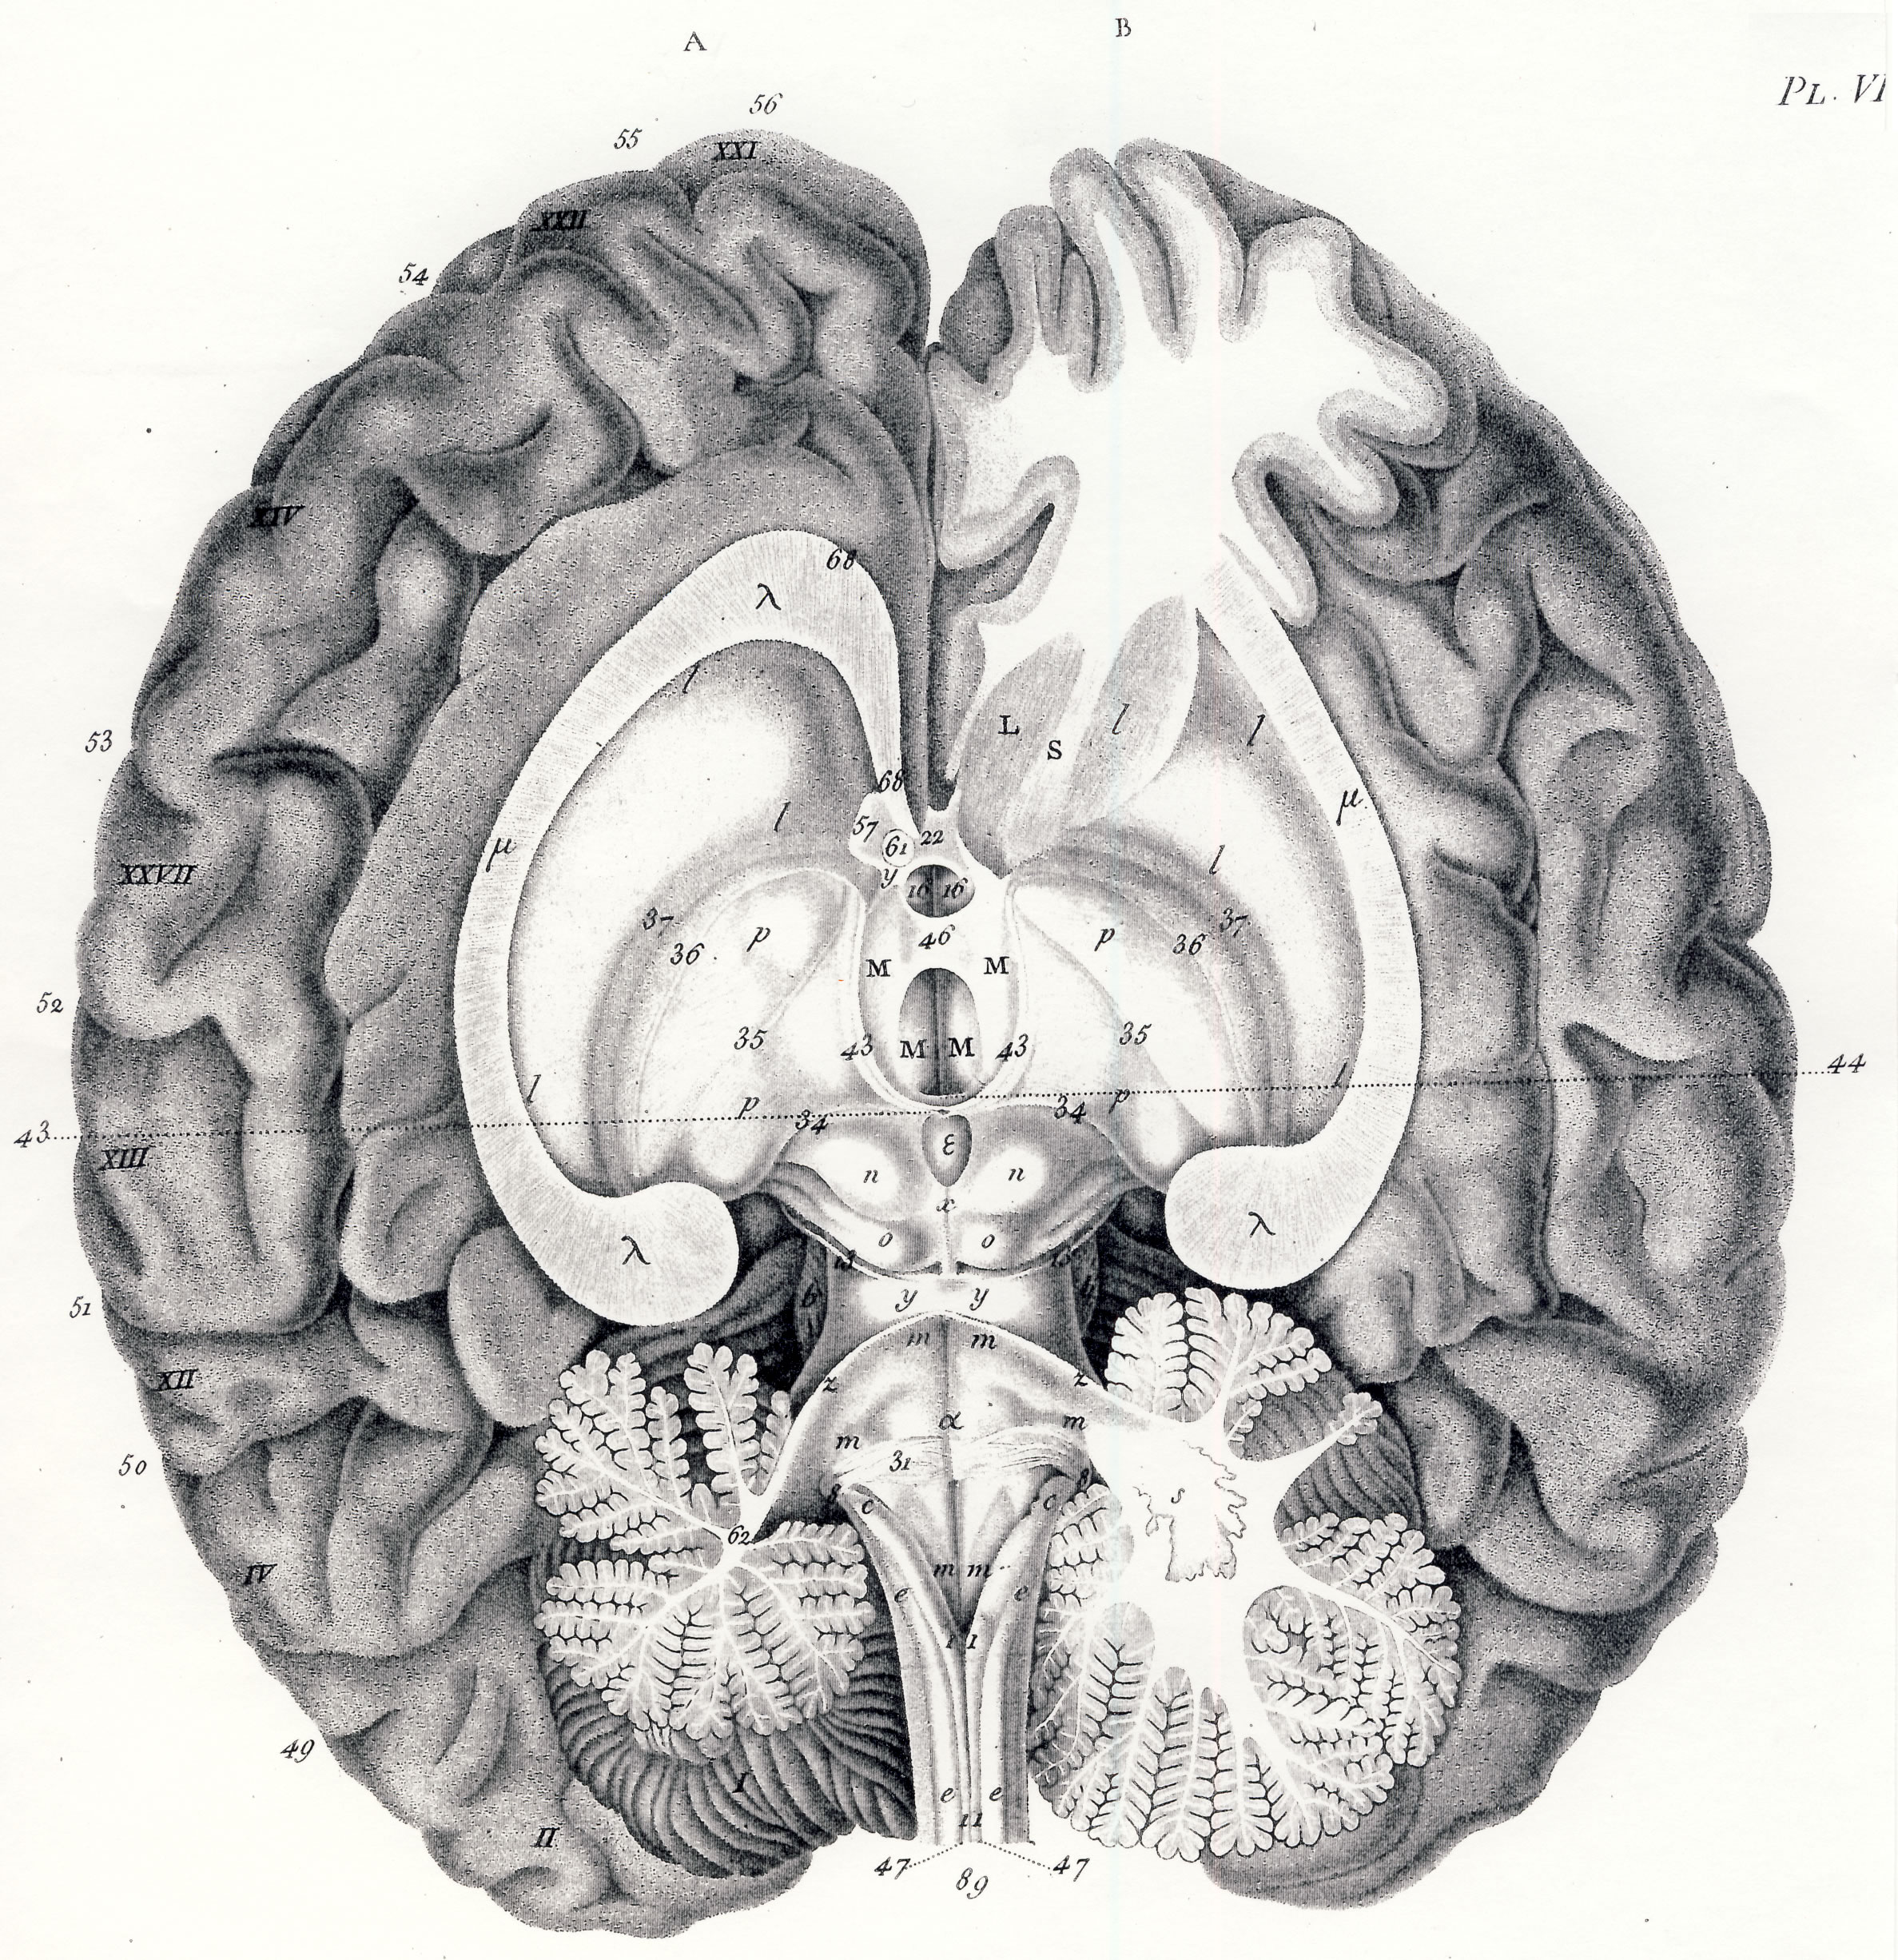

Gall, F. J. (1818). Anatomie et physiologie du système nerveux en général, et du cerveau en particulier, Avec des observations sur la possibilité de reconnoître plusieurs dispositions intellectuelles et morales de l´homme et des animaux, par la configuration de leurs têtes.

Librairie Grecque-Latine-Allemande, Vol. 3, I-XXXV u. 1-379 100 planches.